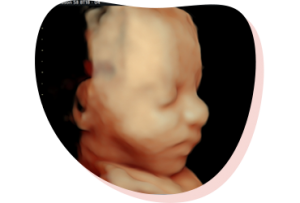

De 3/4D pretecho

(tussen 24-30 weken)

Voor de duidelijkste pretecho’s in 3D en 4D is het belangrijk dat er nog genoeg vruchtwater in de buik is. Vanaf week 30 neemt de hoeveelheid vruchtwater af. Ben je volslank, in verwachting van een tweeling of ligt de placenta aan de voorzijde van de buik, dan raden we je aan om nog voor de 26 weken te komen.

3D echo

Een 3D echo is een stilstaand beeld van een levensechte weergave van jouw kindje. Hierbij zijn duidelijke contouren zichtbaar van bijvoorbeeld de vingertjes, het neusje en de lipjes.

4D echo

Je ziet ‘live’ wat je baby doet: gapen, schoppen, draaien, duimzuigen… Met een 4D echo zie je beweging én kleur.